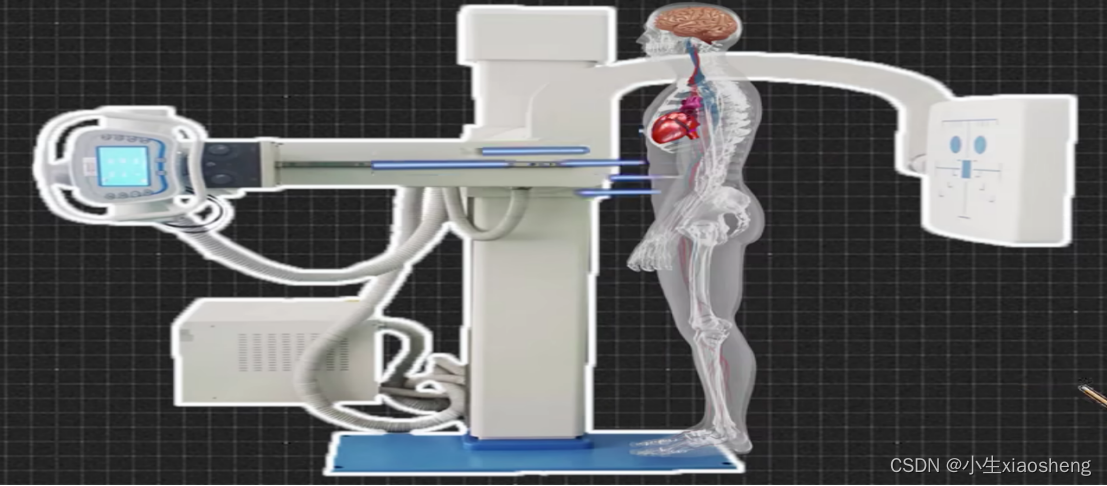

辐射检测:CT和X光

X光:X光检测价格低、时间短、出片快、辐射小,适合前期检查。由于人体各个组织对X线所产生的影响是不同的,所以就有不同的反应实验就是下图

生成的图片为,它把三维的你压缩成二维的图片了,所以可能会丢失信息。